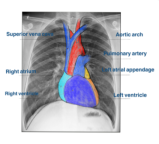

一、正常x线表现

(一)X线平片心脏、大血管的正常投影

1后前位(正位)重点强调后前位胸片上心影轮廓的构成

1心右缘分为两段

上段为主动脉与上腔静脉的总投影

下段为右心房构成

2心左缘分为三段

上段为主动脉结

中段为肺动脉主干

下段由左心室构成

(二)心脏大小的评估及体型与心脏类型的关系

1心胸比的定义和正常值线下课结合移动设备与学生互动,完成选择题,了解知识点掌握情况,酌情讲解。